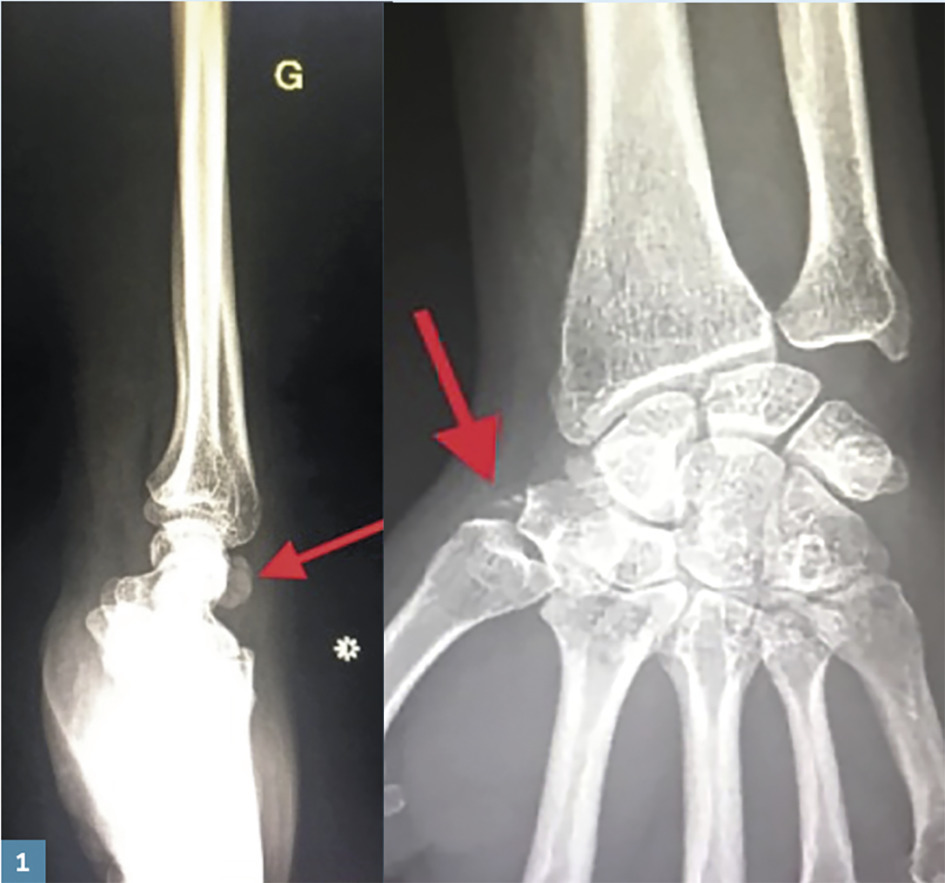

Une femme de 45 ans consulte pour une douleur spontanée qu’elle a depuis quelques jours au niveau du poignet gauche, irradiant à la colonne du pouce, accompagnée d’une impotence fonctionnelle (fig. 1 ).

À la radiographie du poignet : calcifications en regard du bord radial du trapèze et de la face dorsale du carpe, en faveur d’une arthropathie microcristalline.

Le diagnostic est fait en général à la radiographie. Les cristaux d’apatite contiennent du phosphore et du calcium : ils apparaissent donc distinctement sur les clichés sous l’aspect de calcifications arrondies. Celles-ci se distinguent d’une ossification par l’absence de structures trabéculaires, l’homogénéité radiologique et l’apparence arrondie de leurs densités.